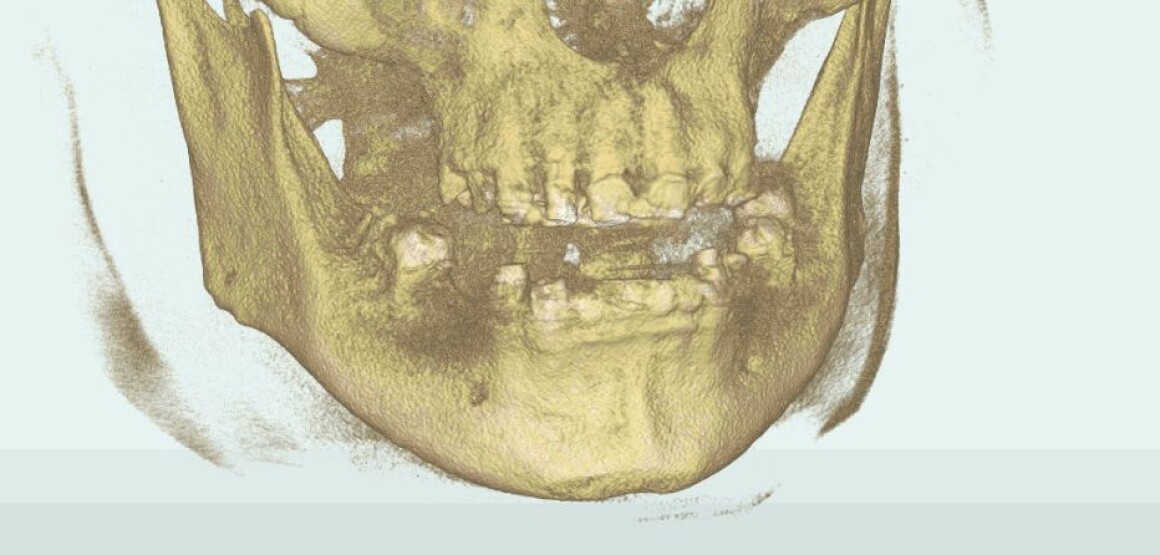

Проблема : Полное отсутствие зубов, не держаться протезы

• Имплантация 12 имплантантов за один раз